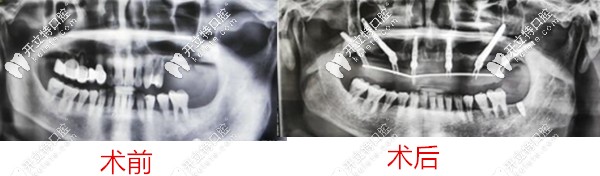

2、弟弟,60歲

種牙前牙齒問(wèn)題:全口牙松動(dòng)、多顆缺失,牙槽骨流失;

種植方案:雙側(cè)穿顴穿翼,種植6顆恢復(fù)14顆。